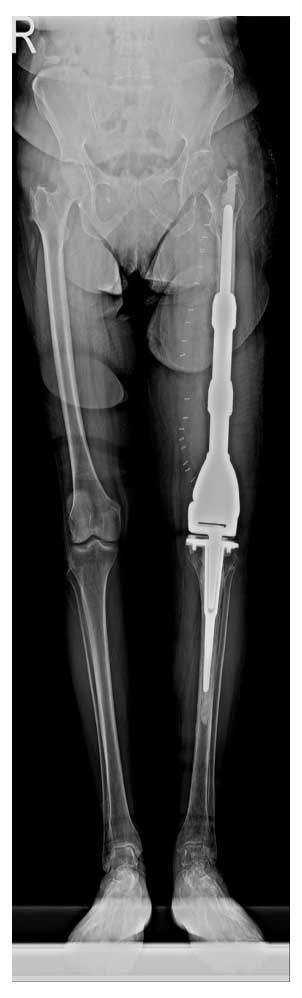

Ameliyat Sonrası: Röntgende rezeksiyon sonrası uygulanan tümör protezi görülmekte.